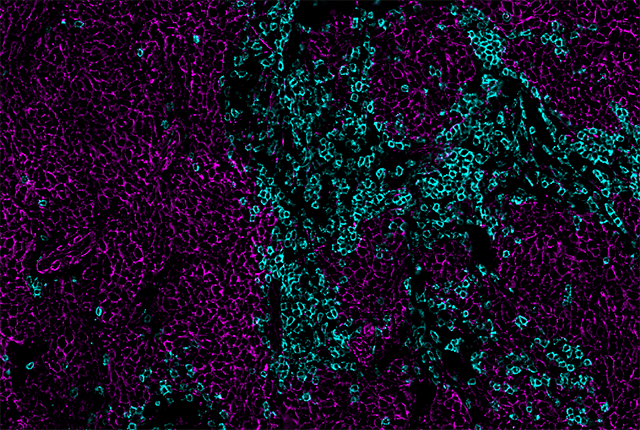

New work from two teams of scientists at Fred Hutchinson Cancer Center and the University of Washington School of Medicine reveal a biomarker that predicts which patients with the aggressive skin cancer Merkel cell carcinoma will respond to a type of cancer immunotherapy.

In papers (one, two) published Feb. 9 in Cell Reports Medicine, the researchers showed that it’s the frequency of anti-tumor immune cells in a Merkel cell cancer patient’s blood, not the tumor, that predicts whether their tumor will respond to immune checkpoint inhibitors. The findings are a step toward the development of a clinical test that could someday guide treatment of the disease.